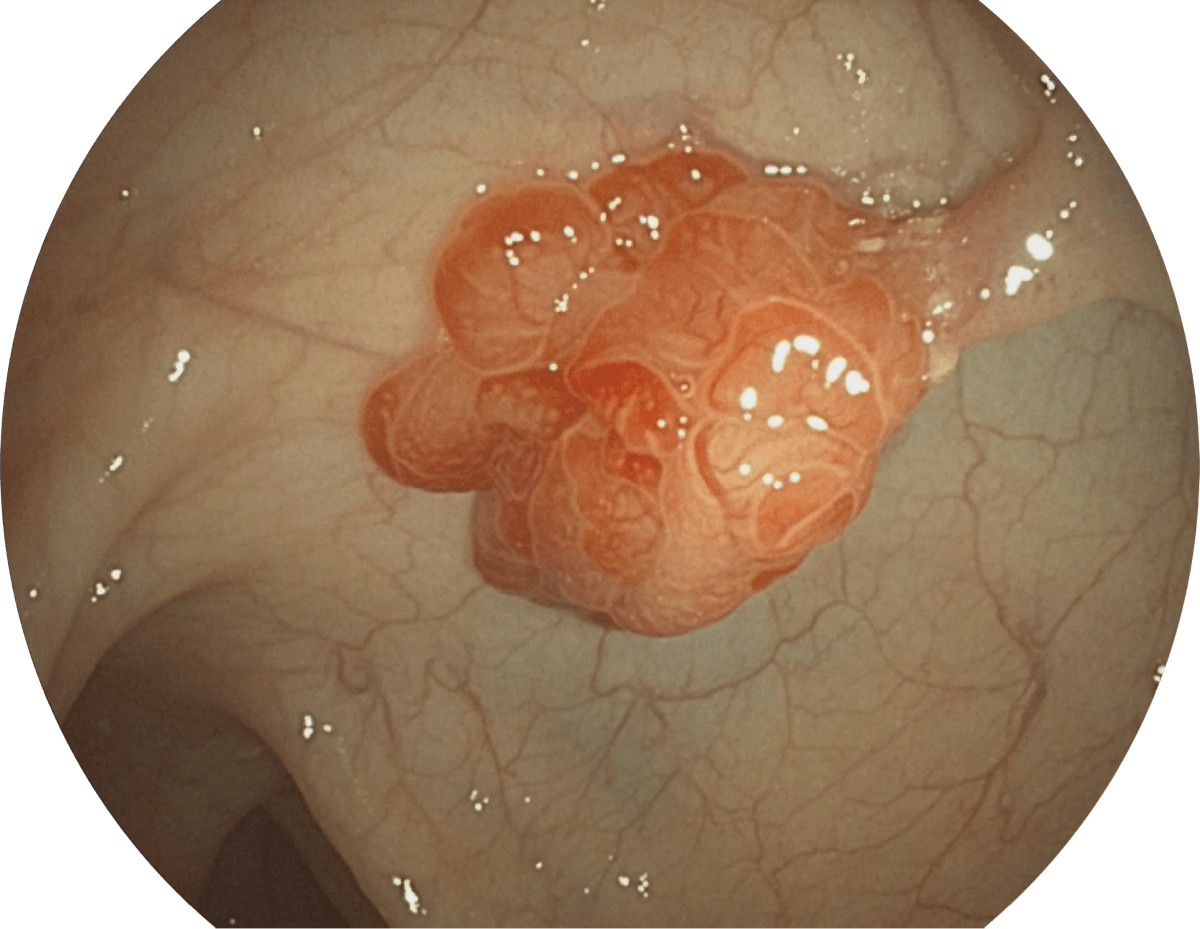

具有聚谱成像技术(SFI)及光电复合染色成像技术(VIST),可完美呈现粘膜细节及病变特征。

(Spectral Focused lmaging, SFI)

SFI